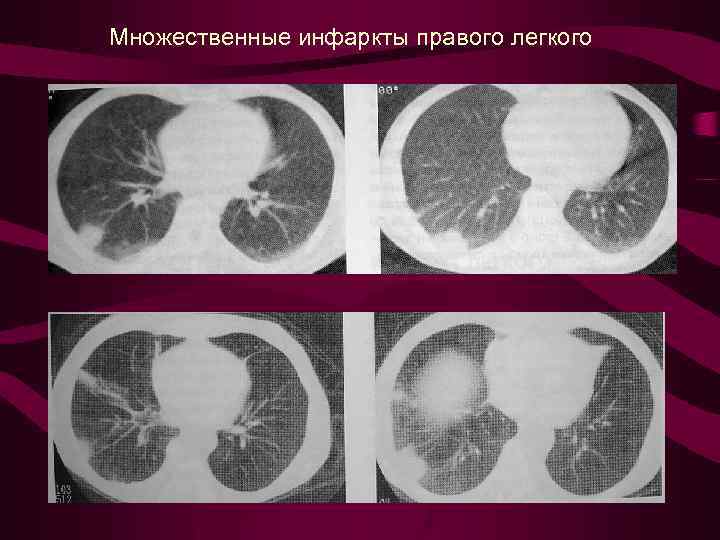

Множественные инфаркты правого легкого

Множественные инфаркты правого легкого